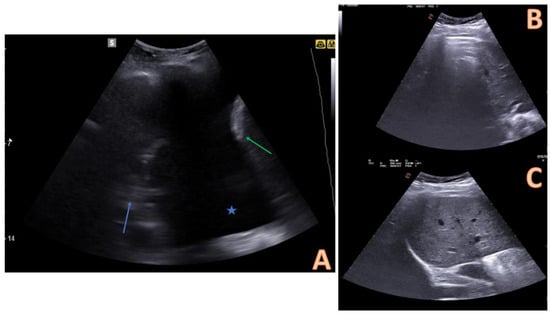

7. Ultrasound-Guided Thoracentesis

9. Complications